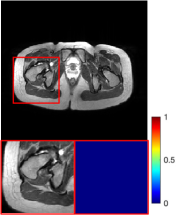

4.3 Qualitative results

Figure 5 provides the qualitative comparison of the various methods on the four datasets at a scale of 4. The top, second, third, and bottom rows are the SR results under the FastMRI, clinical brain, clinical tumor and clinical pelvic datasets, respectively. The red boxes indicate the zoom-in region of complicated anatomical structures along with their corresponding error maps. Note that the brighter textures in the error maps, the lower the quality of the reconstructed images. As can be seen, compared to methods based on Transformers and CNNs, diffusion-based methods like DisC-Diff and DiffMSR (Ours) are capable of reconstructing high-realistic images with promising reconstruction metric scores (PSNR and SSIM). Nevertheless, while DisC-Diff can reconstruct high-precision MR images, it does not preserve the structure present in the original HR images, introducing some additional information that can affect medical diagnosis. In contrast, our method combines DM and PLWformer, which can preserve the original image’s structure while restoring high-frequency information.

9 More Visual Comparisons

In this section, we present more visual qualitative comparisons. Figures 8, 9, 10, and 11 show the reconstruction results of each method in FastMRI, clinical brain, clinical tumor, and clinical pelvic, respectively. As can be seen, although DisC-Diff can reconstruct MR images with high-frequency information, it fails to preserve the structure and content of the original Target HR image effectively, resulting in image distortion. In contrast, our proposed DiffMSR can restore high-frequency information while preserving the structure of the original HR image, indicating the effectiveness of the joint use of DM and PLWformer.